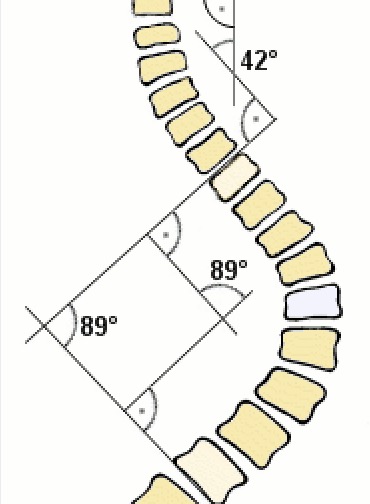

- Cobb's angle���Ʋ��ǣ� ���Ǽ�������������� ��2020-02-27

- Cobb�� ���壺Cobb�DZ�������������ȷ�����ټ�������Ľ�չ��Dr John Cobb ��1948�귢�������ַ������������壺Cobb�ǰ���ҽ��������Ҫʲô�������ơ� .....